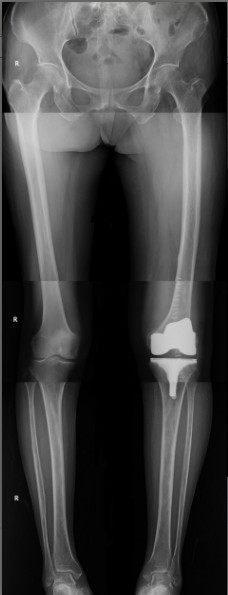

病例三:患者女性,66歲。主因“右膝疼痛4年多”入院。入院前患者有4年多時(shí)間不能正常行走,每次下地需扶墻行走,每次只行走幾米遠(yuǎn)。

患者術(shù)前

患者術(shù)后

患者術(shù)后全長